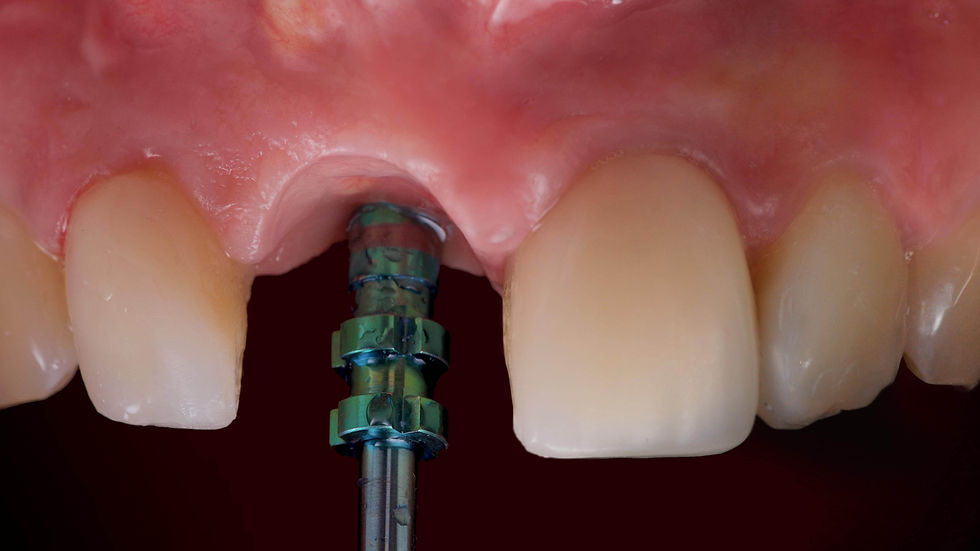

Surgical template positioning on the opened flap, for better soft tissue management.

Prama RF implant in place. The convergent neck allows the ability to manage the irregular residual bone levels and the surrounding soft tissues, avoiding “bone augmentation” and leaving room for the clot which will turn into new gingiva.